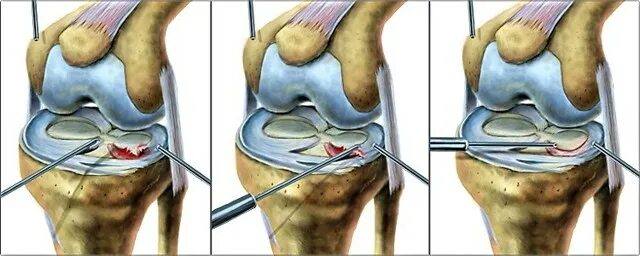

Разрыв заднего